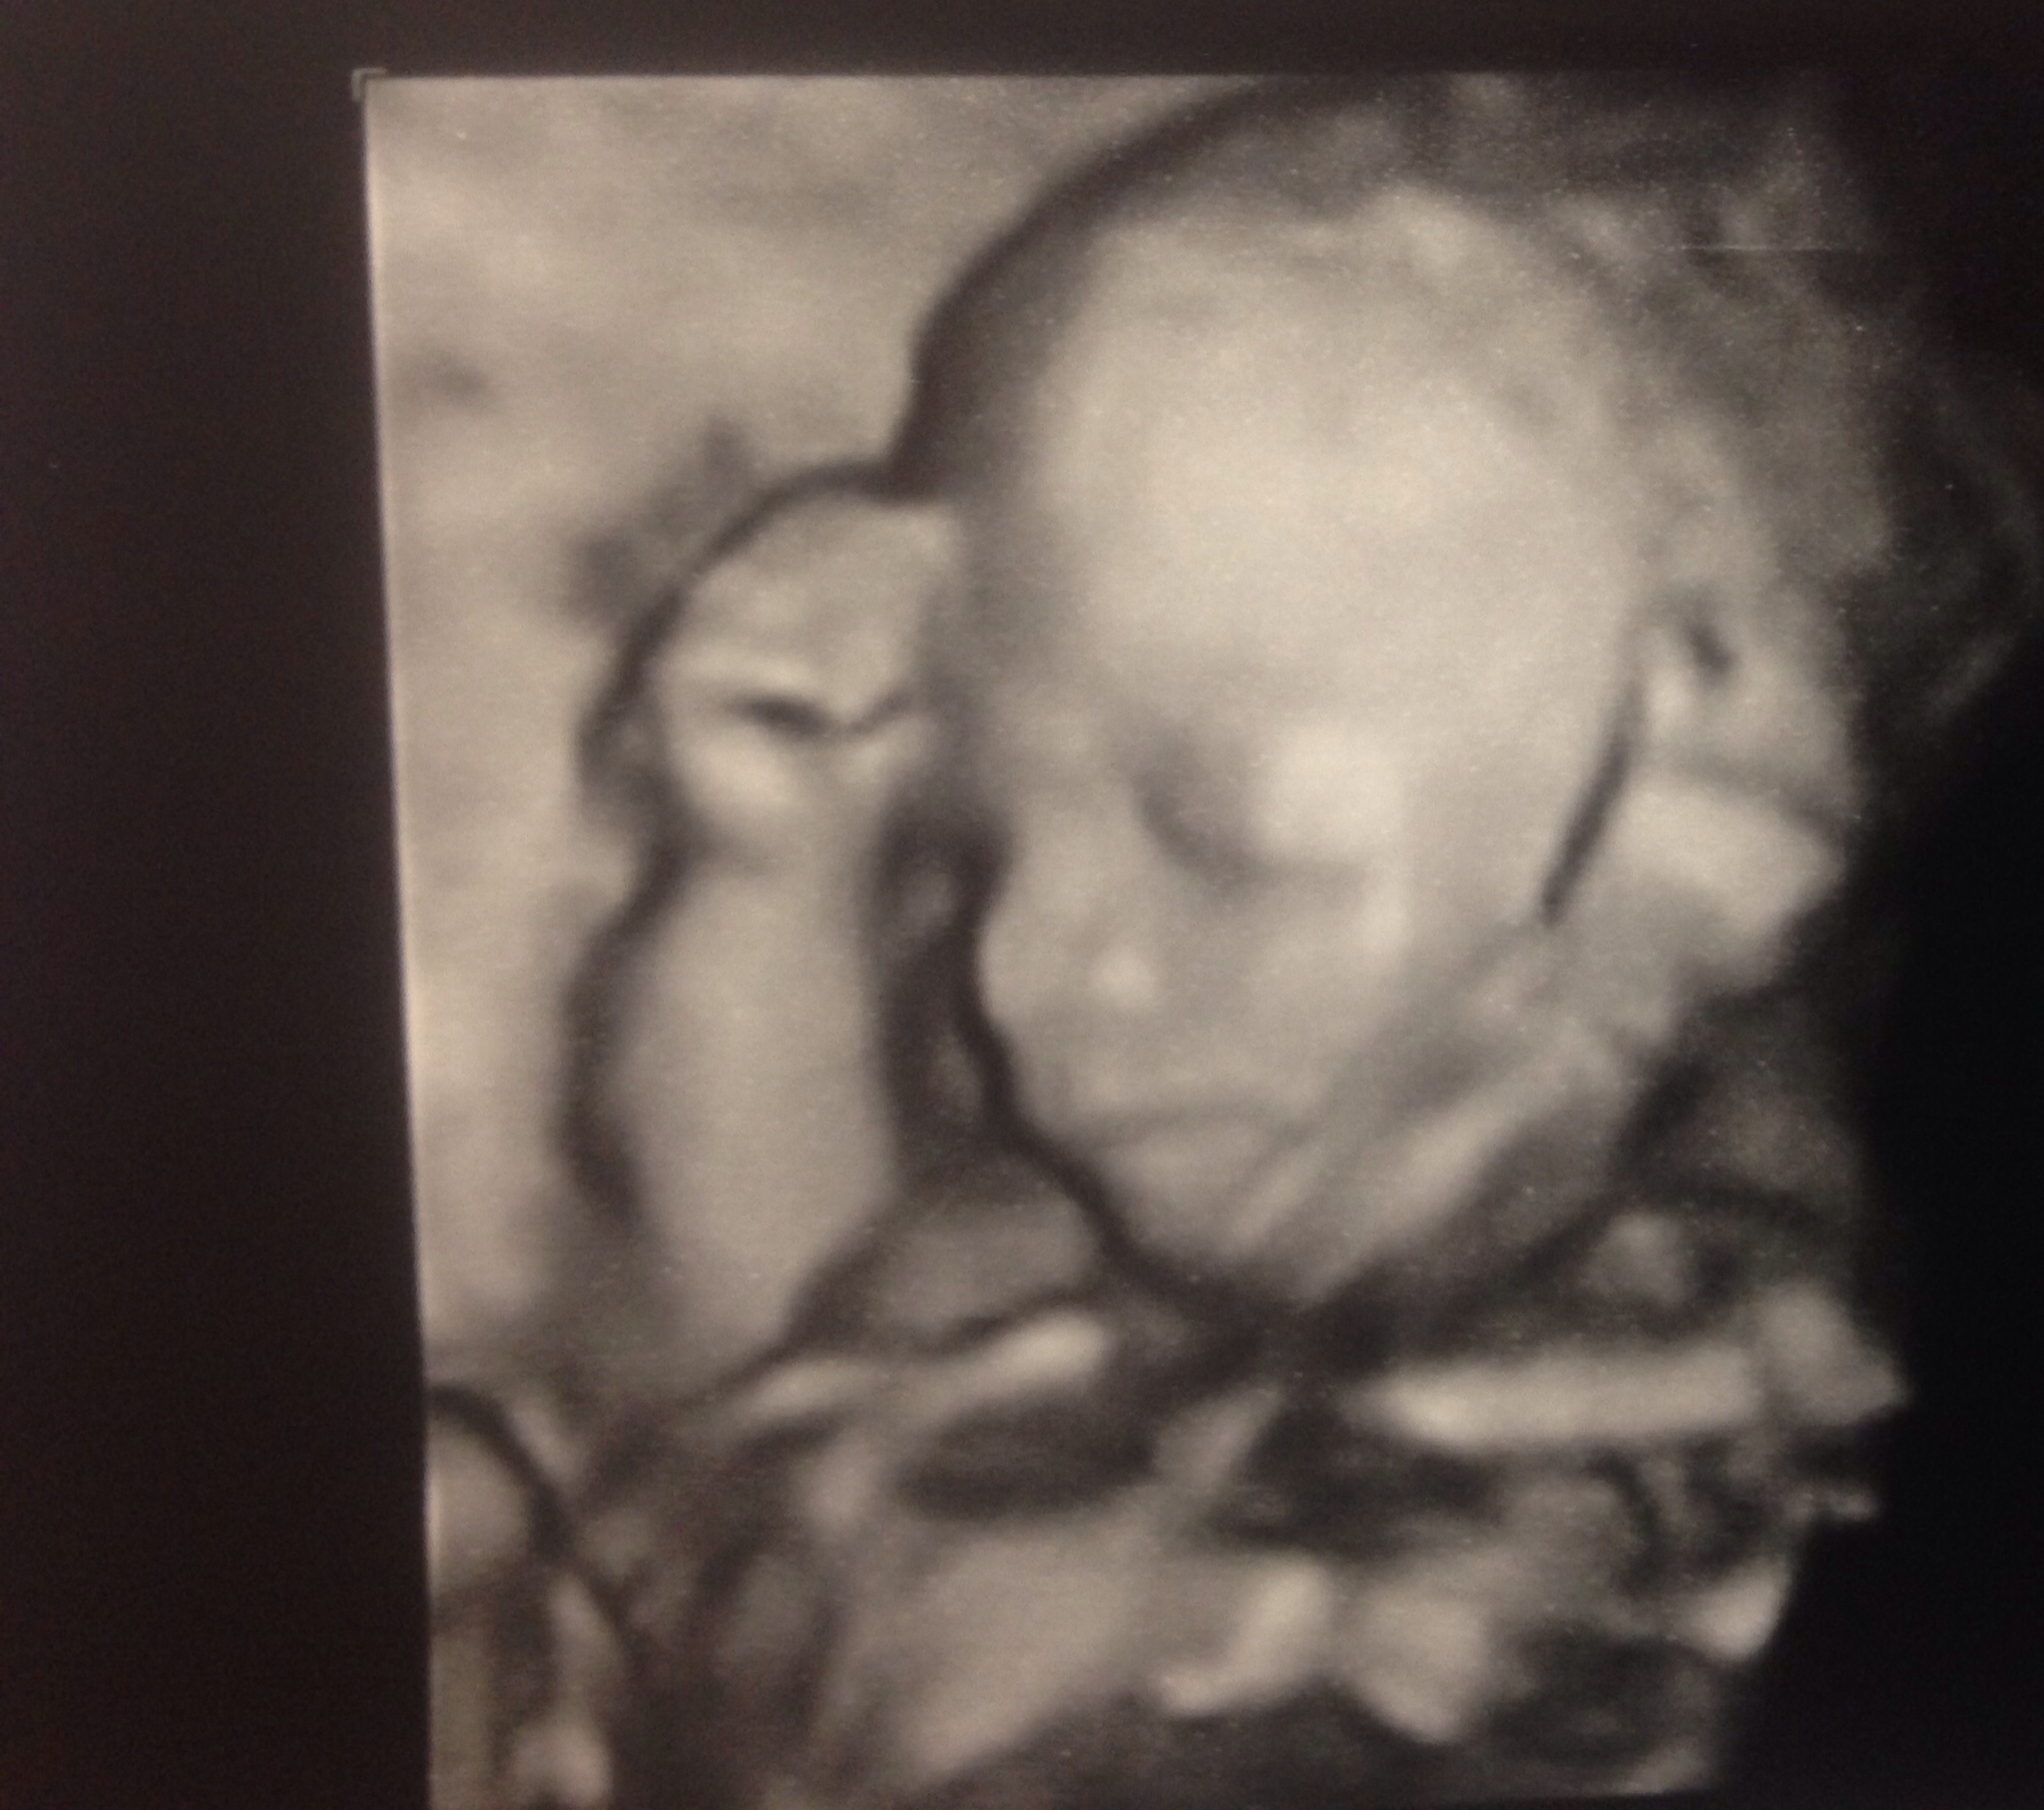

Such a Beautiful baby! Congratulations OP!